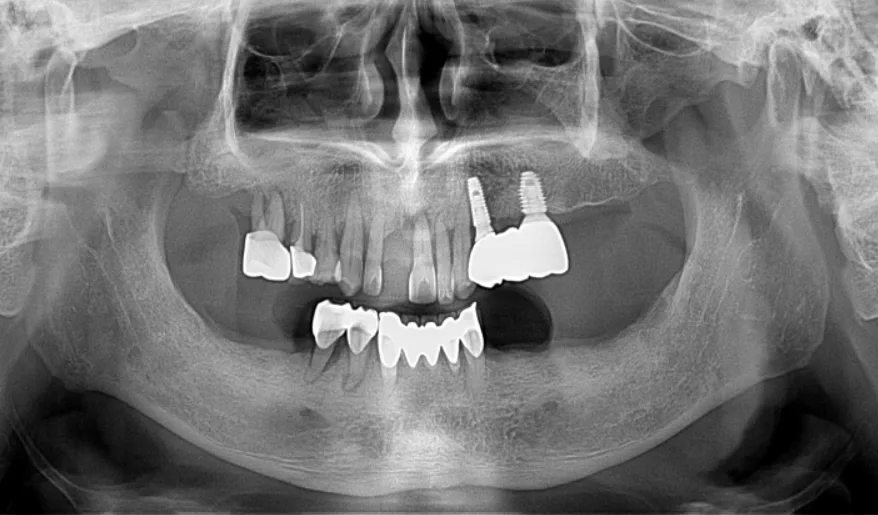

임플란트 이야기를 해봅시다

요약입니다 이건. 컬럼내용요약